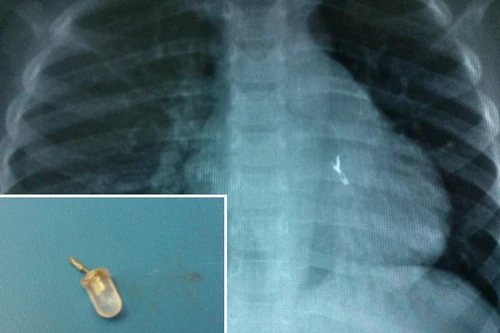

Báo động tình trạng hóc dị vật ở trẻ em

ANTĐ - Trong vòng nửa tháng trở lại đây, tại Hà Nội và TP.HCM đã tiếp nhận và cấp cứu nhiều trường hợp hóc dị vật ở trẻ nhỏ. Đáng báo động, những trường hợp này đều là các bé nhỏ, hóc phải những dị vật nguy hiểm, ảnh hưởng đến tính mạng.